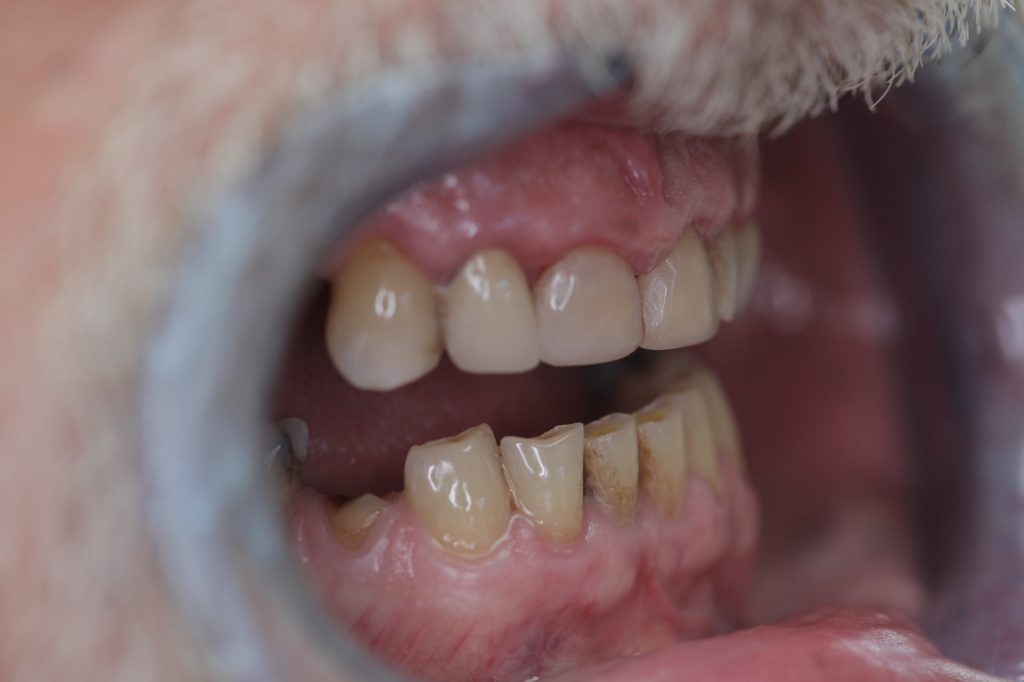

Multiple front teeth fillings, edge restorations using Asteria composite (Case presentation) (54)

A male patient, aged 67, reported to our clinic with the aim of having his condition assessed. He received a detailed treatment plan for his dental problems, which meant the fabrication of a full-arch bridge for his upper jaw. During the patient’s 2-day stint in Hungary we tried to focus on dealing with the most critical problems.

The front teeth were filled using Tokuyama Asteria Estelite filling materials.